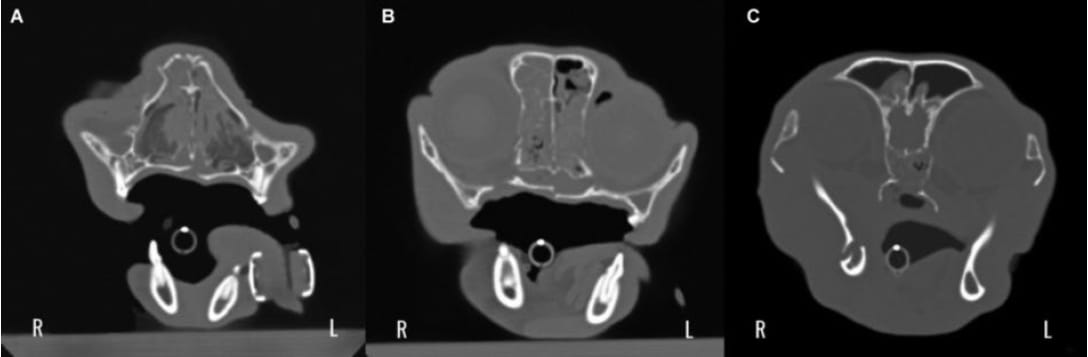

(A–C) Typical multifocal fracture pattern impacting the respiratory, olfactory and digestive system combined with orbital lesions and

fracture of the pterygoid process (25/48 cats), making a multimodal therapeutic approach necessary.